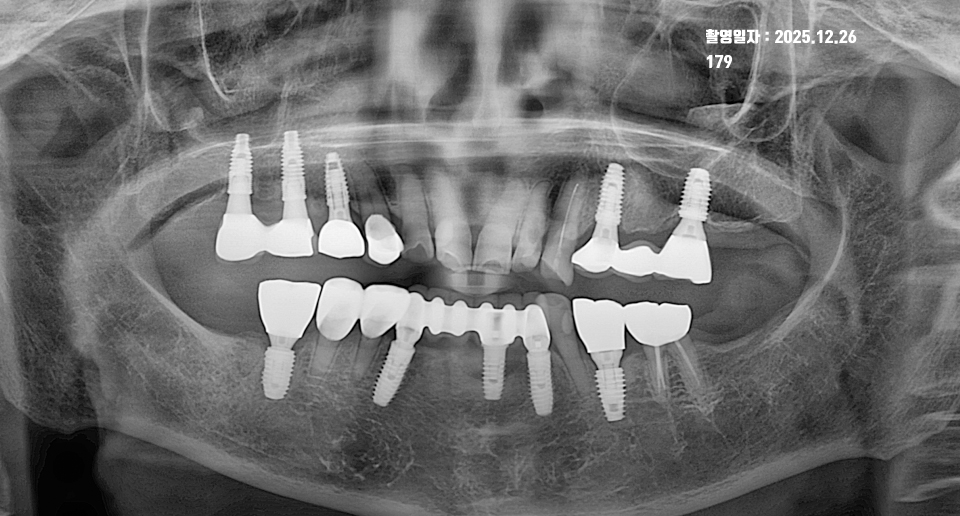

2. 2024년: 11년 경과 후 정기검진 (장기 유지기)

두 번째 사진은 그로부터 약 11년이 흐른 2024년 12월의 모습입니다. 그사이 추가적인 임플란트 식립도 진행되었지만, 기존 임플란트의 상태에 주목해 주세요.

- 치조골의 유지: 11년이라는 긴 시간이 지났음에도 불구하고, 임플란트 주변 치조골의 높이가 2014년과 비교했을 때 거의 변화 없이 견고하게 유지되고 있습니다.

- 임플란트 주위염 방어: 임플란트 실패의 주원인인 ‘임플란트 주위염(골소실)’ 증상 없이 깨끗한 상태입니다. 이는 환자분의 철저한 구강 위생 관리와 정기적인 치과 검진이 동반되었음을 보여줍니다.

위 사진 비교에서 보듯 11년 전후의 뼈 높이가 일정하다는 것은 다음과 같은 의미를 가집니다.